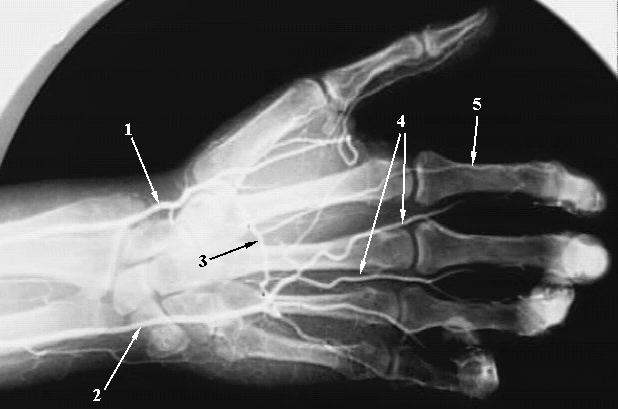

Upper Limbs:Hand Angiogrm Arches:

1. Radial Artery

2. Ulnar Artery

3. Deep Palmar Arch

4. Common Palmar digital Arteries

5. Proper Palmar Digital Artery.